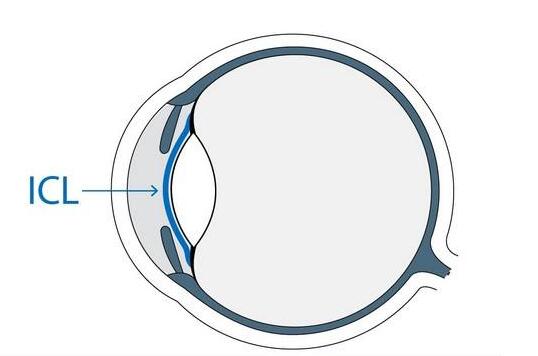

在王先生倍感失望之际,安徽理工大学附属眼科医院近视医治中心李波主任为他推荐了ICL植入术。王先生在选择近视手术之前,了解过多种近视手术的方式,了解ICL植入术,所以他当即选择了ICL植入术来 自己的近视。医院为他做了进一步检查,为其在瑞士定制了两枚ICL晶体。上周四,李波主任在制定了周密的手术方案之后,为王先生 实施ICL晶体植入术。 二天术后检查时,才有了开头那激动的一幕。